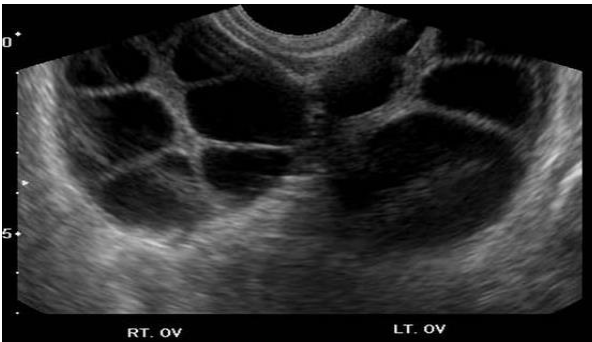

when a pt is undergoing ovarian hyperstimulation, the US recording the mean follicle diameter should be performed in the

.

a) luteal phase

b) early follicular phase

c) late follicular phase

d) menstrual phase